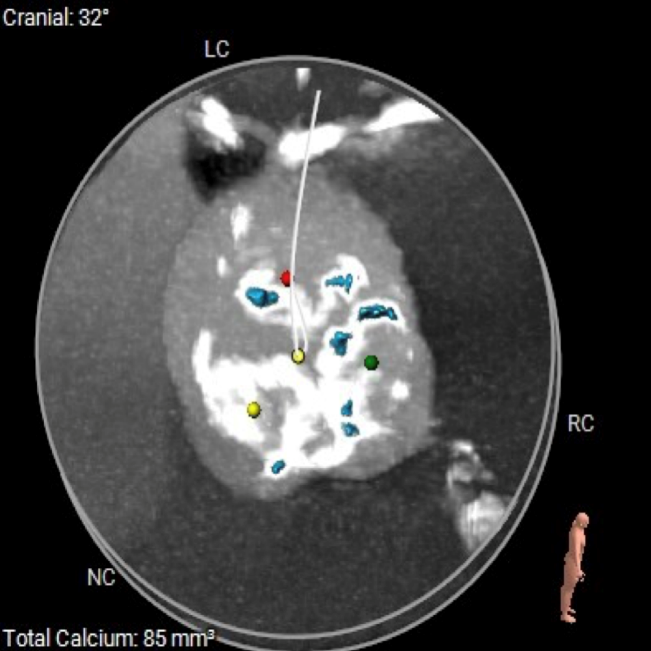

CT数据显示该患者为Type0主动脉瓣。

主动脉瓣瓣环周长97.1mm,平均周长径 30.9mm,SOV:34.8mm*47.5.3mm*42.4mm,瓣叶增厚,瓣上钙化分布不均,瓣环水平夹角66°。

钙化分布:HU850钙化积分881mm³